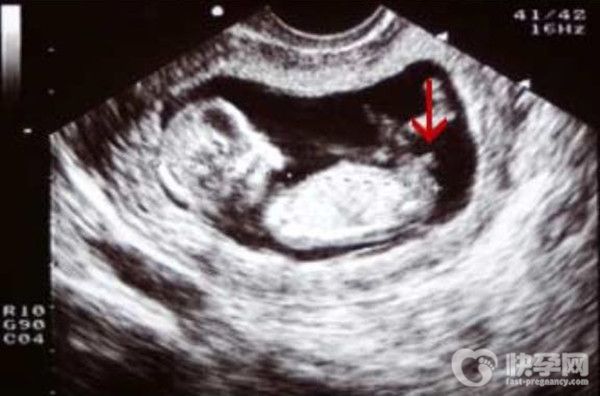

2.通过nt图看男女

但是,通过nt图看男女,无非是看胎儿的姿势。很多人说nt图如果是弯曲的,一般是男生,如果是平行的,一般是女生。据说还可以看胎儿的脊线。如果大于30度,男生的几率高,如果小于30度,女生的几率高。